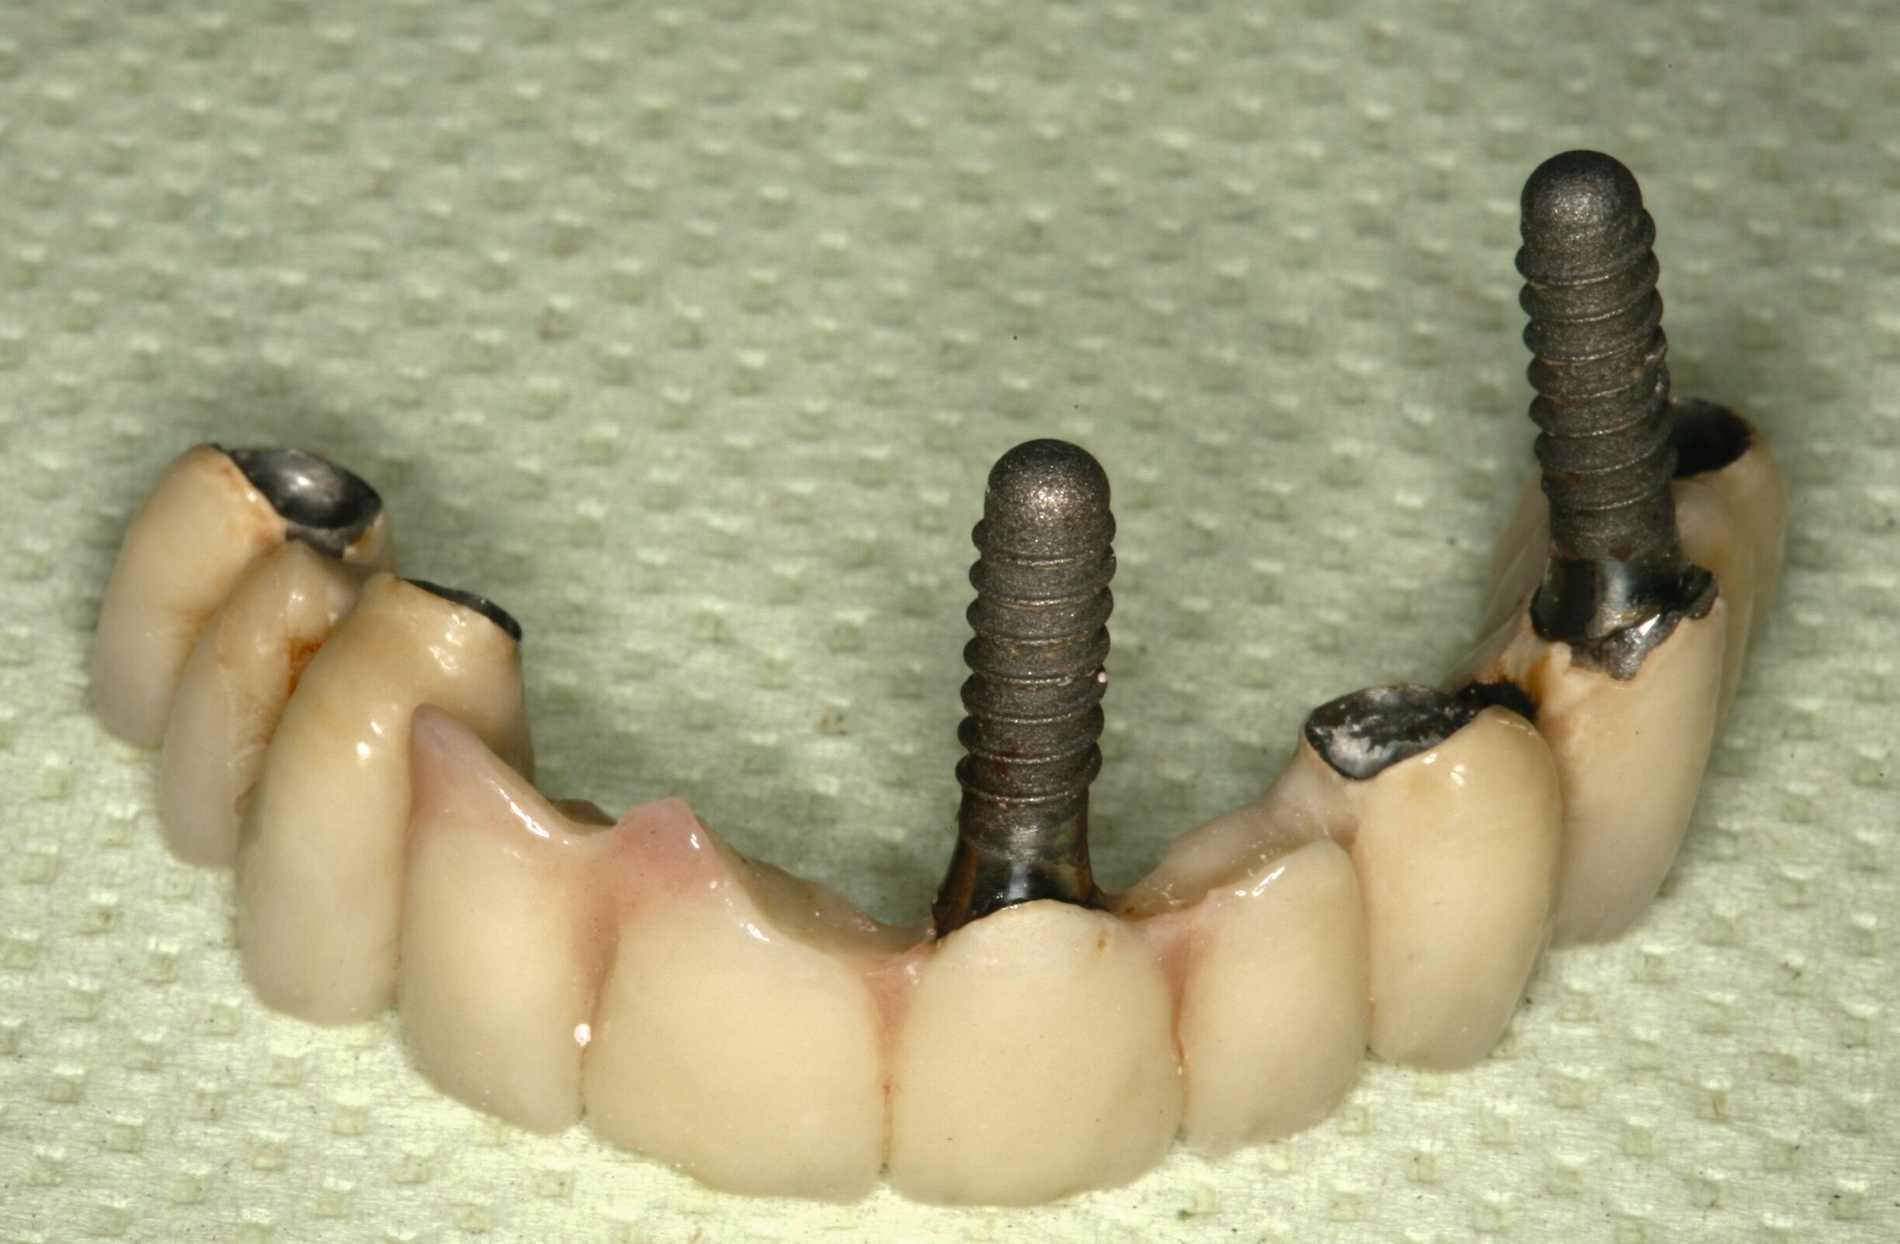

So bieten kombiniert zahn- und implantatgetragene Doppelkronenprothesen eine ausreichende Stabilität bei Reduktion der Basis im Bereich des Gaumendaches. Die Prothesen haben einen ausreichenden Halt und die verbliebenen Zähne werden entlastet. Die Literatur zur sogenannten strategischen Pfeilervermehrung zeigt gute Überlebensraten von Implantaten (> 92 Prozent) und Suprakonstruktionen (100 Prozent) nach fünf Jahren [Bassetti et al., 2018; Lian et al., 2018; Molinero-Mourelle et al., 2022]. Tragen Patienten schon Prothesen und Pfeiler gehen verloren oder sind ungünstig verteilt, dann können Implantate unter dem vorhandenen Zahnersatz für eine bessere Abstützung, ein besseres Kauvermögen und eine höhere Zufriedenheit sorgen [Wolfart et al., 2013; Wolfart et al., 2016]. Dies funktioniert natürlich auch mit kostengünstigen Miniimplantaten, wie eine kürzlich beendete prospektive randomisierte Drei-Jahres-Studie zeigen konnte (Abbildung 7) [Al Jaghsi et al., 2021; Mundt et al., 2020; Mundt et al., 2022]. Falls einteilige Miniimplantate in der Altenpflege wegen Entzündungen oder Bissverletzungen Probleme bereiten, können die Retentionsköpfe problemlos mit Diamant- oder Hartmetallfräsen abgetrennt werden und die Schraube im Knochen verbleiben.